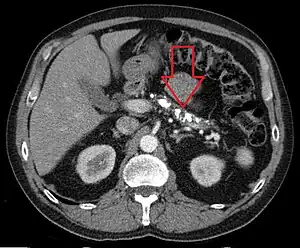

On CT scan, pancreatic and bile duct dilatation, atropy of pancreas, multiple calcifications of the pancreas, and enlargement of pancreatic glands can be found.[12]

On MRI scan, there is a low T1 signal due to inflammation, fibrosis, focal lesions, and calcifications. In those who are given with a contrast agent, there would be a higher T1 signal with late gadolinium enhancement due to compression from the fibrotic areas. The overall thickness of the pancreas will be reduced. Magnetic resonance cholangiopancreatography (MRCP) is the most useful option in accessing the pancreatic duct and bile duct.[12]

Chronic calcific pancreatitis

Acute on chronic pancreatitis